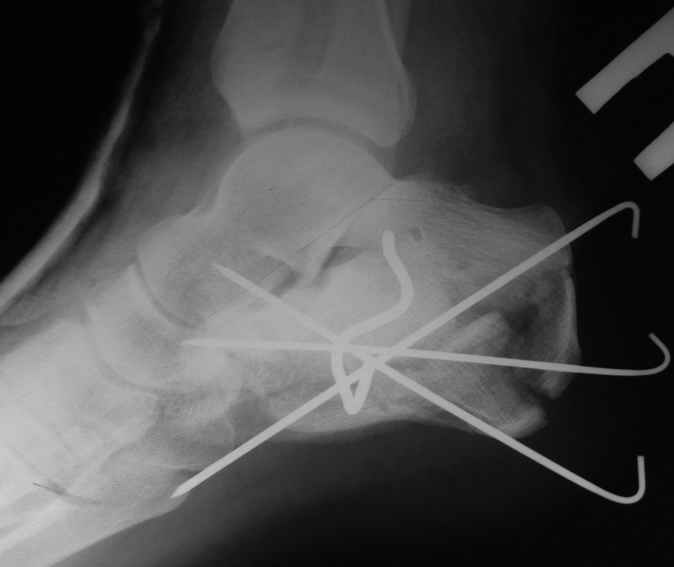

В/суставные переломы пяточной кости у молодых являются показанием к оперативной коррекции, Большой материал накоплен у д-ра Дрягина (Челябинск). В нашем отделении предпочтение отдаем открытой репозиции, при наличии выраженного отека, фликтен и т.д.

Накладываем спицевой дистрактор, позволяющий выхаживать м/ткани и одновременно устранять захождение отломков.

Окончательная фиксация спицами, пяточными пластинами (5) , в последнее время стали применять крючковидные пластины (ДЕОСТ) (6,6a).

Кроме стандартных снимков, необходим контроль конгруэнтности суставной поверхности (проекции Бродена)